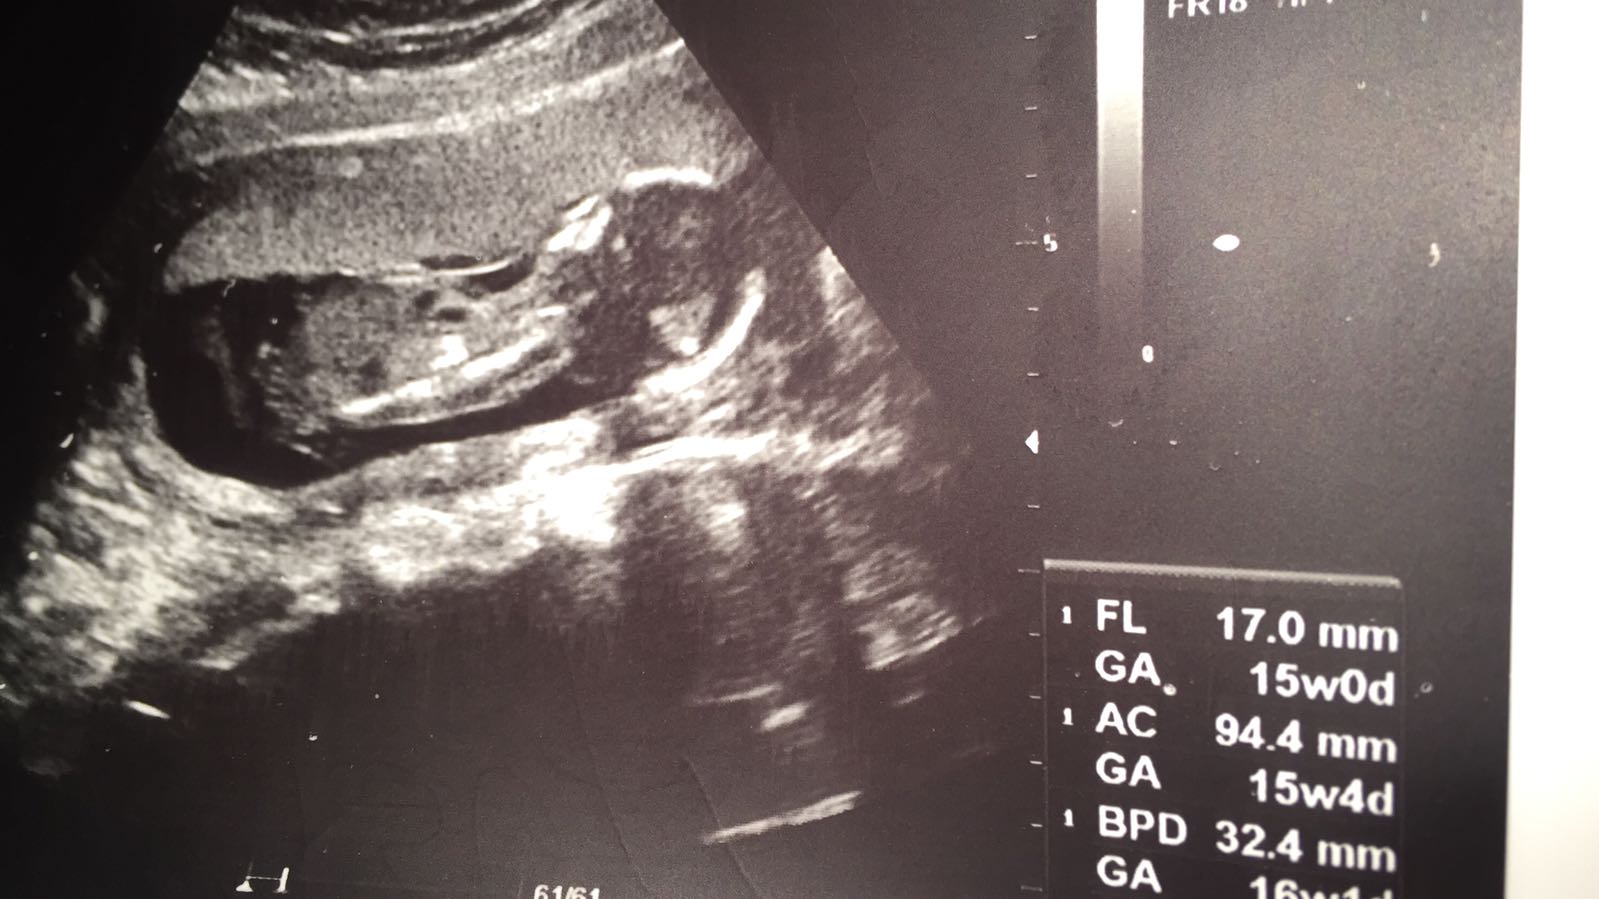

Bebegimin cinsiyeti?? Nub Teorisine göre nedir kızlar

Merhaba hanımlar. Yüklemiş olduğunuz görsellerin kalitesi iyi değil. Nub çıkıntısını göremedim. Bu nedenle bebeğinizin cinsiyeti hakkın da tahmin yürütemiyorum.